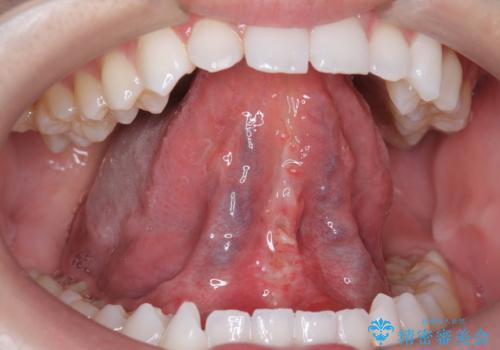

切除後、しっかり上にもつくようになり、前にも大きく出せるようになりました。

発音については、大人よりも子供の方が効果が期待できますが、舌の可動域が増えるため、おすすめです。た行、ら行などは、舌を上につけないと舌足らずになってしまします。